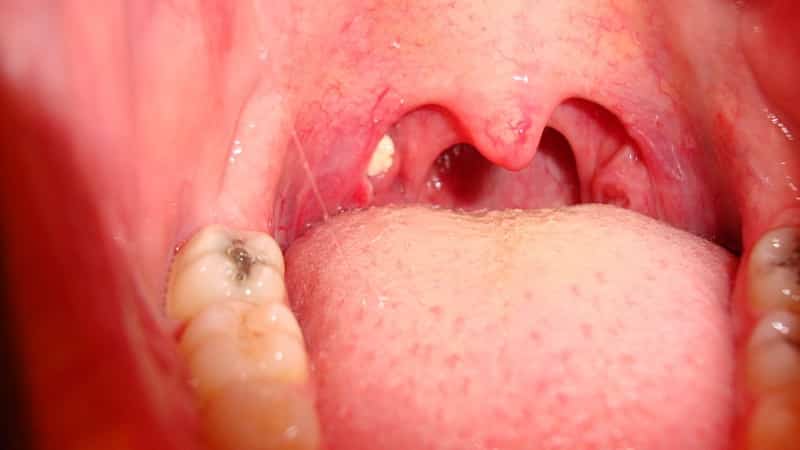

Острый и хронический тонзиллит. Это, пожалуй, самая распространенная причина появления белых точек на миндалинах. Заболевание представляет собой воспаление гланд, вызванное патологической микрофлорой. Острая гнойная форма характеризуется накоплением гноя в лакунах миндалин, что выглядит как плотные белые и желтоватые пробки, которые легко удаляются с помощью ватного тампона. Хроническая форма подразумевает постоянное наличие небольших пробок, которые нужно периодически удалять и полоскать горло. В этой форме, как правило, отсутствуют другие симптомы.

Если возникает ангина на фоне тонзиллита, у пациента наблюдается покраснение и воспаление горла, болезненность при разговоре и глотании, резкое повышение температуры, а гнойники увеличиваются в размере и становятся потенциальными источниками распространения инфекции по организму.